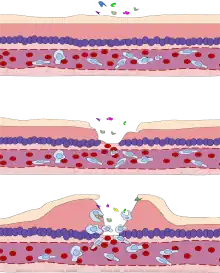

This type of guidance has hampered efforts that could prevent airborne transmission, such as measures that improve ventilation of indoor spaces and limits on indoor gatherings, say the researchers in the commentary: “We are concerned that the lack of recognition of the risk of airborne transmission of COVID-19 and the lack of clear recommendations on the control measures against the airborne virus will have significant consequences: people may think that they are fully protected by adhering to the current recommendations, but in fact, additional airborne interventions are needed for further reduction of infection risk.” - Since the 1930s, public-health researchers and officials have generally discounted the importance of aerosols — droplets less than 5 micrometres in diameter — in respiratory diseases such as influenza. Instead, the dominant view is that respiratory viruses are transmitted by the larger droplets, or through contact with droplets that fall on surfaces or are transferred by people’s hands. When SARS-CoV-2 emerged at the end of 2019, the assumption was that it spread in the same way as other respiratory viruses and that airborne transmission was not important.

But other researchers say that case studies of large-scale clusters have shown the importance of airborne transmission. When the news media reported large numbers of people falling ill following indoor gatherings, that caused Kim Prather, an aerosol scientist at the University of California, San Diego, to begin questioning the adequacy of the social-distancing recommendations from the US Centers for Disease Control and Prevention (CDC), which call for people to stay 6 feet (1.8 metres) apart. The indoor spread suggested the virus was being transmitted in a different way from how health authorities had assumed. “For an atmospheric chemist, which I am, the only way you get there is you put it in the air and everybody breathes that air,” says Prather, who joined the commentary. “That is the smoking gun.” - Laboratory studies going back to the 1930s and 1940s concluded that droplets expelled through talking or coughing are larger than aerosols. These bigger droplets, more than 5 micrometres in diameter, drop out of the air quickly because they are too heavy to ride on light air currents.

But more-sensitive experiments are now painting a more complex picture that points to the importance of aerosols as a transmission route. A study published in May used laser-light scattering to detect droplets emitted by healthy volunteers when speaking. The authors calculated6 that for SARS-CoV-2, one minute of loud speaking generates upwards of 1,000 small, virus-laden aerosols 4 micrometres in diameter that remain airborne for at least 8 minutes. They conclude that “there is a substantial probability that normal speaking causes airborne virus transmission in confined environments”.